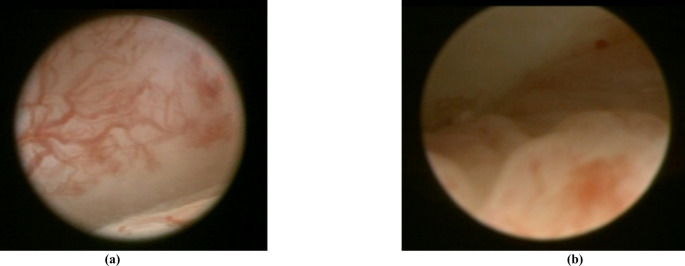

Methods: Non-experts for the purposes of this study were recruited from German dental students. After a focused instruction on TMDs, they completed two evaluation rounds to identify and assess selected pathologies of arthrogenic TMDs in patient cases. Initially, participants were provided with MRI images only; in a second round, additional arthroscopic video material was provided. Statistical analysis was performed to evaluate responses, and inter-rater reliability among non-experts was determined.

Results: 94 participants evaluated a total of 30 MRI scans of the temporomandibular joint (TMJ) obtained from 27 patients who had also undergone arthroscopy. Their assessment showed the relatively highest agreement with the correct diagnosis for disc perforations (68.2-71.9%) and when using both MRI and arthroscopy material. Synovitis showed the lowest agreement, and was more successfully detected based on arthroscopy (47.2%) alone. Overall, there was only slight to fair agreement among the study participants across diagnoses (Kappa 0.074-0.358). Non-experts showed significant inconsistencies in interpreting MRI and arthroscopic imaging, with only limited concordance with the actual diagnosis and an agreement rate of less than 71.9%.